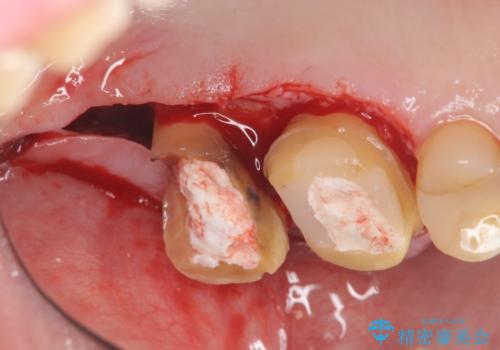

・深い虫歯 →歯周外科を行うことで歯ぐきの腫れを改善

・根尖性歯周炎 →精密根管治療

・咬合機能の回復 →セラミッククラウンの製作

と問題点を一つづつ丁寧に解決し、長期的に虫歯が再発せず安定を見込める治療を行っていきます。